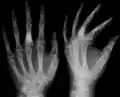

X-ray image showing enchondromas localized in the lower part of the radius of a 7-year-old girl with Ollier disease.

Abnormal bone growth such as shortening or thickening and deformity may be observed in patients of Ollier disease. These bone lesions are visible at birth using radiography but are usually not screened or examined for until clinical manifestations present during early childhood. However, some patients may exhibit no signs of any symptoms.[1] One study found thirteen to be the mean age of diagnosis in patients with Ollier disease. In an X-ray, there would normally be the presence of several homogeneous lesions of an oval or elongated shape with bone edges that are slightly thickened.[3] With age, these lesions may calcify and appear as diffusely minute spots or stippled. Fan-like septations or streaks would be indicative of the presence of several enchondromas. Early detection and consistent and repeated monitoring is important in order to prevent and treat any potential bone neoplasms.